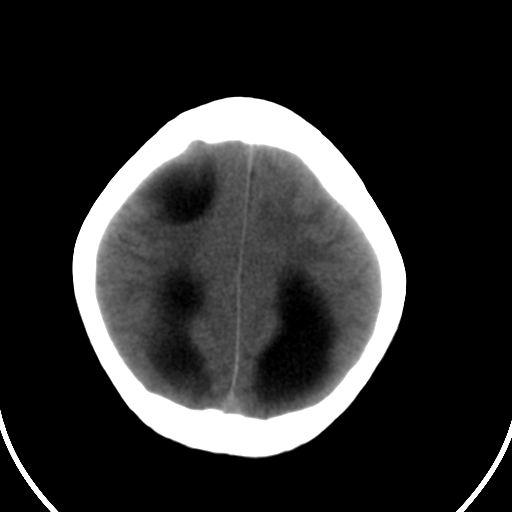

男,11岁

右额叶单发近圆形低密度影,周边光滑,与侧脑室相通,考虑为孔洞脑并阻塞性脑积水。

右额叶内见一边界清楚,脑脊液密度的囊腔,无灰质内衬,并与脑室相通,四室以上脑室系统高度扩张。诊断:先天性脑穿通畸形伴梗阻性脑积水

需要与脑裂畸形鉴别:可见单侧或双侧衬有皮层的脑裂伸入额顶叶的白质内并与脑室相通

脑穿通畸形并梗阻性脑积水.

脑穿通畸形囊肿脑积水